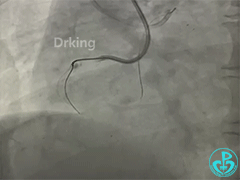

AL1,微导管辅助下XTA、P200导丝无法前行,感觉近段纤维帽坚硬。

导丝怎么扩收藏:器械难以通过的CTO病变之技术图谱_https://www.jmylbn.com_新闻资讯_第9张

下一步怎么办?何种方式更快速高效?

1.Power puncture;

2.Scratch and go(选择更硬的CP8-20);

3.Base;

4.Side-Base;

5.Power-knuckle;

6.Carlino;

7.双腔微导管辅助下的Puncture;

8.启动逆向等。

1.CTA提示严重钙化,逆向直接通过概率低,选择逆向也得进行必要的前向准备,决定首先采取正向技术,突破近段纤维帽尤其关键;

2.由于无边支、入路不明显,可选用Base、

Power-knuckle、Carlino组合以希望突破近段纤维帽。